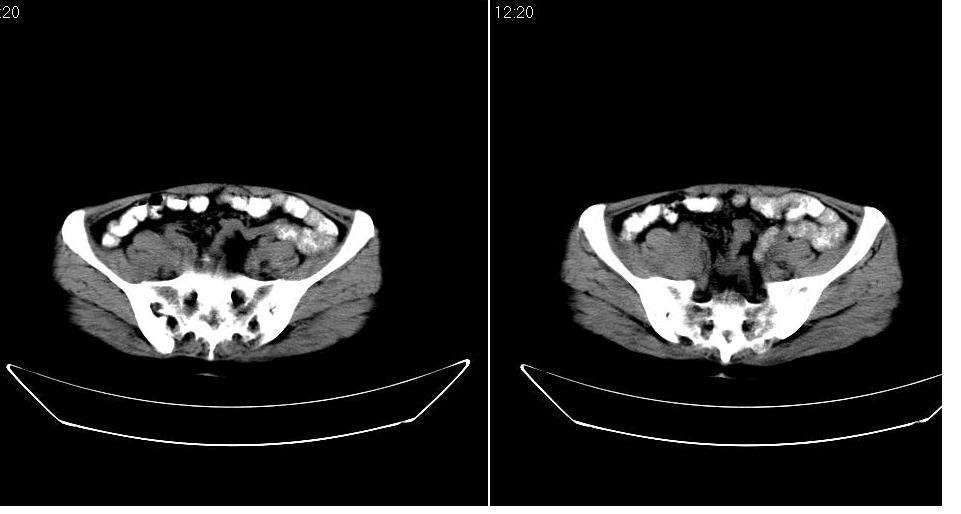

女 53岁,大便每天四到五次,变细,伴有粘液,病人家属说,去年五月在外院行子宫肌瘤术。

腹膜后多发肿大淋巴结肿大并融合改变;右侧回盲部可见团块样软组织影,不规则;

腹膜后诸多淋巴结,右侧髂窝软组织块影,综合患者大便次数、形状改变,考虑结肠回盲部肿瘤

考虑回盲部肿瘤并腹膜后淋巴结转移,建议钡剂灌肠或增强检查。

回盲部可见团块样软组织影,不规则;腹膜后多发肿大淋巴结肿大并融合改变;考虑回盲部肿瘤并腹膜后淋巴结转移,建议钡剂灌肠或增强检查.

双侧盆腔均可见不规则形软组织肿块影,似为结节状影融合而成,但以右侧为甚,腹主动脉与下腔静脉周围亦可见多个肿大淋巴结.

结合临床手术史考虑:盆腔与腹膜后多发性淋巴结转移(原发灶可能是原来的\"子宫肌瘤\"恶变或并非\"子宫肌瘤\";回盲部肿瘤不排除)